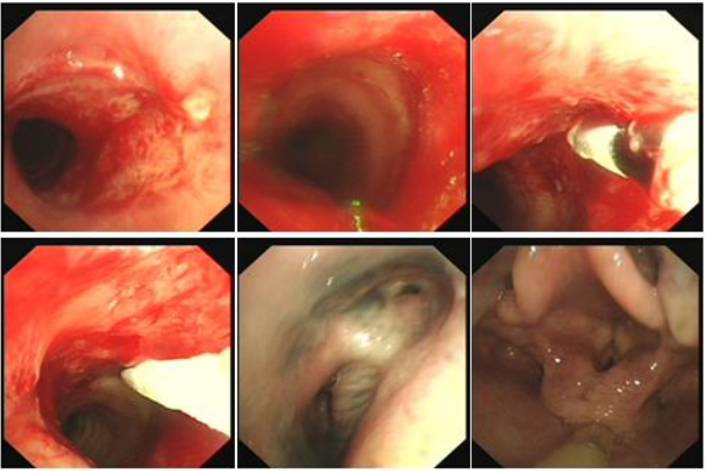

病例2:33岁,男性,全身多处淋巴结肿大1年,气促12天入院(2024年2月22日)。术前(2月22日):被动体位(前倾坐位,不能平卧),HR 136次/min,R 36次/min,SpO2 90%(FiO2 60%)。术前影像学如图24所示。紧急行气管镜检查:气管下段重度外压性狭窄,仅见缝隙,不能窥见隆突,软镜直视下置入金属覆膜支架(MTN-18/50)(图25),支架远端近隆突,术后气促明显改善。术后第4天(2月26日)咽部异物感明显,气促加重,复查胸片支架移位。再次行气管镜示:声门下腔见金属支架,经口取出支架,置入部分覆膜支架(18/40)(图26),支架远端近隆突,术后气促明显改善。B超引导下肿大淋巴结多点穿刺提示为弥漫大B淋巴瘤,后续行淋巴瘤相关治疗。病例3:64岁,女性,咳嗽、咯血、气促1个月入院(2021年12月11日)。气促明显但能平卧,HR 91次/min,R 24次/min,SpO2 94%(吸氧4 L/min)诊断未明确。外院转入。支气管镜检查:左、右主支气管内见新生物,左主混合性闭塞;右主狭窄,右中间段开口见缝隙(图27)。无外科手术指征,采取介入治疗。软镜局麻静脉镇静镇痛(咪唑安定+舒芬太尼),高频通气备用,术前使用甲基强的松龙40 mg静推,治疗策略为分步走,先处理左主,保证氧合:①左主置入导丝以备紧急情况下能快速置入支架;采用生理盐水加压注射法,支气管镜强行进入置入导丝;②充分冲洗清理左肺大量黏稠血性分泌物,防止分泌物溢出导致窒息。处理后患者氧合改善。再处理右主:①探查右中间段(缝隙),生理盐水加压注射法,支气管镜进入右中间段支气管,充分冲洗治疗;②右主支气管冻切活检(少量出血)明确诊断。下一步处理:首选Y型覆膜支架或双侧支气管支架置入,因患者诊断未明确、经济原因及考虑肿瘤的后续有效治疗,放弃Y型支架;左主混合性狭窄,仅在左主置入金属裸支架,右主新生物内镜下切除(冻切+APC)(图28)。2天后复查支气管镜, 左主支架膨胀良好, 右主及右中间支气管予以冷冻冻切残余新生物及消融后焦痂, 治疗后管腔较前进一步通畅(图29)。病例4:52岁,男性,重度呼吸困难,急诊2021年12月20日入院。气管镜检查:隆突浸润明显增宽(鳞癌),左/右主支气管重度外压性狭窄,左侧更明显(仅见缝隙)。第一步,先探查狭窄最重的左主,生理盐水加压注射进入左主,仅左主起始部重度狭窄,清理分泌物,同时置入导丝备用。第二步,探查右主,右上叶支气管基本正常,右主重度外压狭窄并右中间段开口呈缝隙,在生理盐水加压注射下支气管进入右中间段(仅右中间段起始部重度狭窄),冲洗出大量血性黏稠分泌物,置入导丝(图30)。首选Y型金属支架置入,如果没有Y型支架或缺乏置入Y型支架的技术能力,可以分别在左、右置入直筒支架。第三步:置入Y型覆膜支架(图31),使用刘志光改良的Y型支架置入装置(专利),软镜置入快捷(耗时10 min)。支架规格:18/40-14/30-14/20(右)。置入后,支架膨胀良好,呼吸困难显著改善。